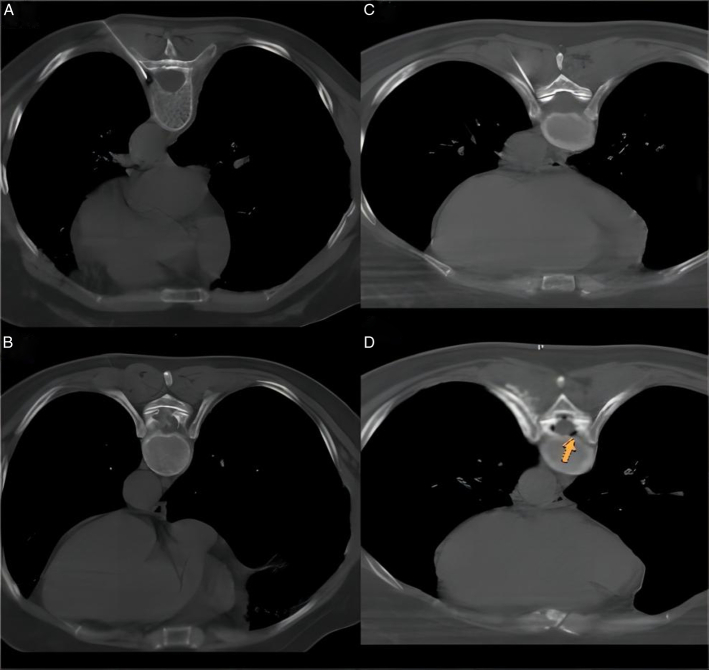

Computed Tomography-Guided Dorsal Root Ganglion Ozone Injection Combined With Pulsed Radiofrequency for Acute Herpes Zoster Neuralgia Treatment of Middle-aged and Elderly People: A Randomized, Double-blinded, Controlled Trial.

Objectives: To investigate the efficacy and safety of pulsed radiofrequency of the dorsal root ganglion combined with ozone injection for treating acute herpes zoster (HZ) neuralgia in middle-aged and elderly adults.

Methods: A total of 164 middle-aged and elderly patients with acute HZ were randomly assigned to 2 groups: the pulsed radiofrequency combined with ozone injection group (group A) and the pulsed radiofrequency group (group B). The therapeutic effects were evaluated using Numeric Rating Scale (NRS) scores and the average doses of gabapentin (mg/d) preoperatively and 1 day, 2 weeks, 4 weeks, 12 weeks, and 24 weeks postoperatively. The incidence of clinically significant postherpetic neuralgia (PHN) and complications in the 2 groups were recorded.